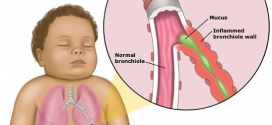

Leer MásHIPERRESPUESTA BRONQUIAL (HRB)

La hiperrespuesta bronquial (HRB). Enfermedad caracterizada por ataques de disnea respiratoria de duración variable con sibilancias y sensación de constricción debida a espasmo bronquial. Reactividad aumentada de las vías respiratorias inferiores a numerosos estímulos: proceso episódico acompañado de obstrucción reversible. Los sintomas más frecuentes son: sibilancias, disnea, fiebre, tos, expectoración, taquicardia, taquipnea, cianosis, insuficiencia de la respiración, hiperinsuflacion, etc. Información: …